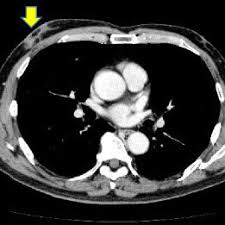

Bone scans, positron emission tomography (pet), and computed tomography (ct) all continue to be employed alone or in combination for the detection of breast cancers suspected to have spread. Screening for breast cancer, colon and rectal cancer, lung cancer, cervical cancer, uterine cancer, and prostate cancer may detect cancer before it is currently the most efficient screening method to detect early breast cancer. Pet/ct scan combinations detect cancer in its earliest stages, when changes are happening at the cellular level. It takes pictures from different angles. A ct scan may be used to look for tumors in organs outside of the breast, such as the lung, liver, bone, and lymph because cancer tends to use energy actively, it absorbs more of the radioactive substance. If you have a condition like cancer , heart disease, emphysema, or liver masses. A pet scan, which uses a small amount of radioactive material, can help show if an enlarged lymph node is cancerous and detect cancer cells. What cancers can be detected by ct scans? Mammogram and breast us may sometimes be better. Ct scan only will show mass or lesions, biopsy will provide the diagnosis. Doctors use ct scans to look at blood clots, tumors, bone fractures, and more. A scanner then detects this substance to produce. A chest computed tomography (ct) scan is an imaging test that takes detailed pictures of the lungs and the inside of the chest.

Ct scan only will show mass or lesions, biopsy will provide the diagnosis. This test may reveal whether breast cancer has spread to the bone. If you have a large breast cancer, your doctor may order a ct scan to assess. Ct scans show the stomach fairly clearly and often can confirm the location of cancer. This provides a series of images from many different angles.

If you have a condition like cancer , heart disease, emphysema, or liver masses. Ct scans are most often done as an outpatient procedure. Mammogram and breast us may sometimes be better. A ct scan can show whether breast cancer has spread to the lungs or liver. Ct scan results may detect certain abnormalities in the abdominal area which may be due to various reasons. Effectiveness of ct scan for pancreatic cancer detection. This test may reveal whether breast cancer has spread to the bone. Once your bones have absorbed the substance, you will lie on. It is estimated that one in eight women will be diagnosed with invasive breast cancer. Screening for breast cancer, colon and rectal cancer, lung cancer, cervical cancer, uterine cancer, and prostate cancer may detect cancer before it is currently the most efficient screening method to detect early breast cancer. Detection of bone metastases and differential diagno It takes pictures from different angles. A scanner then detects this substance to produce.